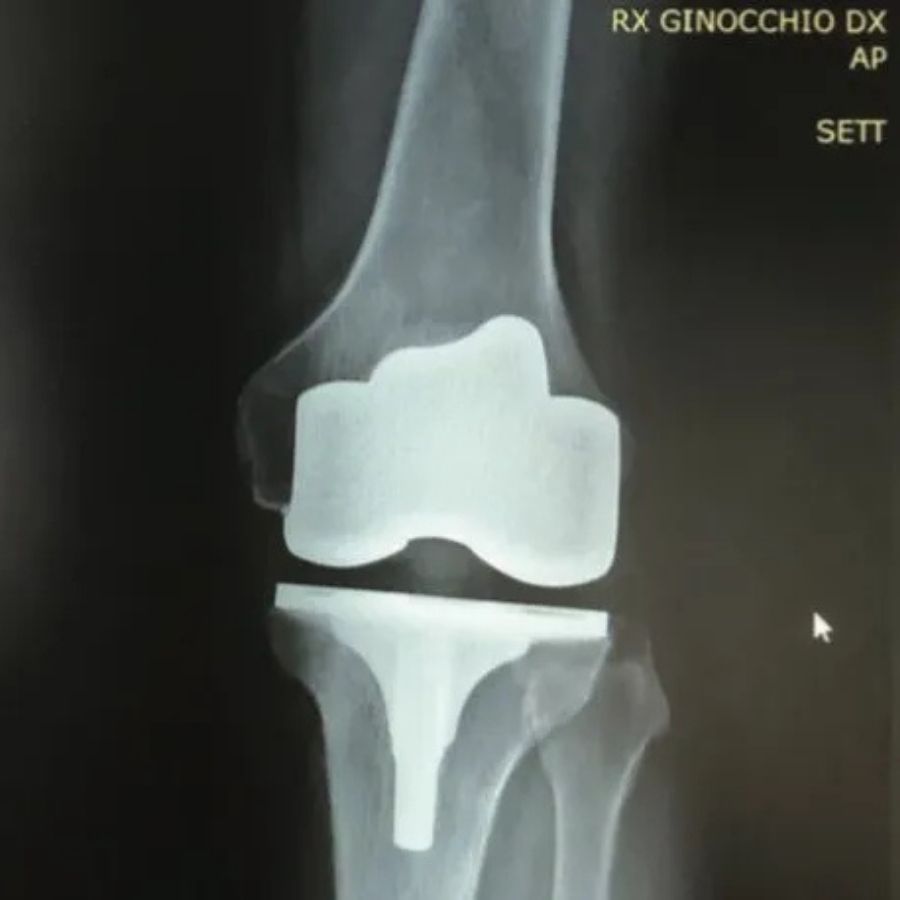

Il Navio , utilizzato dall’ortopedico durante un intervento chirurgico per impiantare una protesi al ginocchio, è un sistema robotico che aumenta la precisione e rende l’intervento chirurgico meno invasivo garantendo anche un allungamento della vita della protesi stessa.

Il sistema robotico Navio permette di posizionare la protesi del ginocchio in modo molto rapido e con una precisione difficilmente eguagliabile dalla mano del chirurgo, per quanto esperto.

Con l’ausilio del Sistema chirurgico Navio l’ortopedico potrà impiantare la protesi più idonea al tipo di lesione su cui si interviene, in quanto la protesi sarà scelta ad hoc in base al movimento del ginocchio ed alla specifica anatomia.

Il chirurgo avrà la possibilità di impiantare la protesi beneficiando di una pianificazione strumentale in tre dimensioni che, grazie al sistema Navio, permette non solo precisione accurata ma anche rapidità nell’esecuzione dell’intervento.

Con questo nuovo strumento computer-assistito il chirurgo trarrà il massimo vantaggio utilizzandolo sia per l’impianto di protesi totale che protesi monocompartimentale.

Il beneficio finale sarà quello di garantire al paziente una durata maggiore della protesi e una migliore funzionalità della stessa.